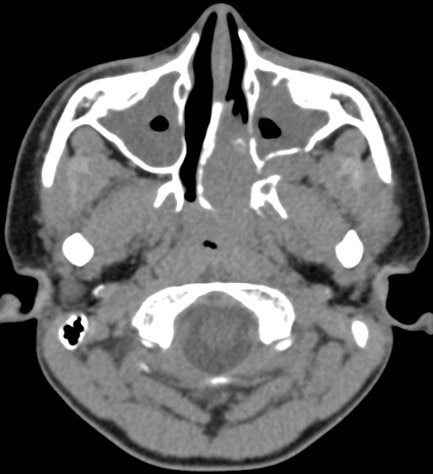

1258. У пациента 13 лет 1,5 года назад появилось затруднение носового дыхания и периодические выделения из носа, на КТ в основной пазухе, распространяясь в ячейки решетчатого лабиринта и носоглотку, разрушая левое большое и малое крыло клиновидной кости и распространяясь в левую крылонёбную ямку, определяется новообразование, активно накапливающее контрастный препарат, с неровными нечеткими контурами, что соответствует